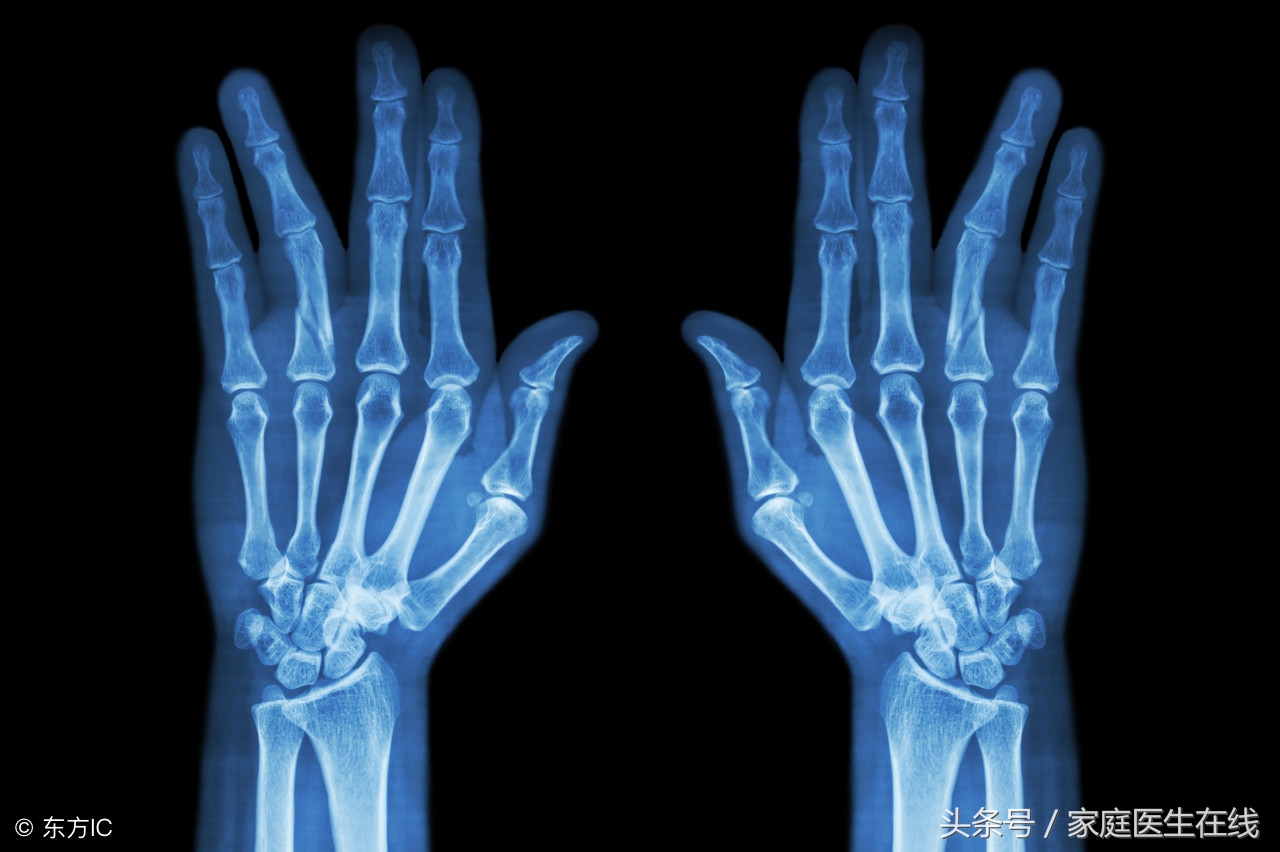

3、还有在运动的时候突然出现抽筋的现象,这个时候就应该要食用一些钙片来为身体补充所需要的钙物质。如果一个人的身体出现了缺钙的现象的话,就会导致骨质疏松。如果经常性的骨质疏松就会很容易导致骨折,而且人体的骨骼变得非常的脆弱。

这是因为如果身体缺钙的话就会让一个人的骨骼变得脆弱,如果经常这样的话就会让骨骼出现断裂的现象。这也是为什么有一些老年人驼背的现象非常严重,所以大家一旦发现身体出现了这些信号就代表身体缺钙。